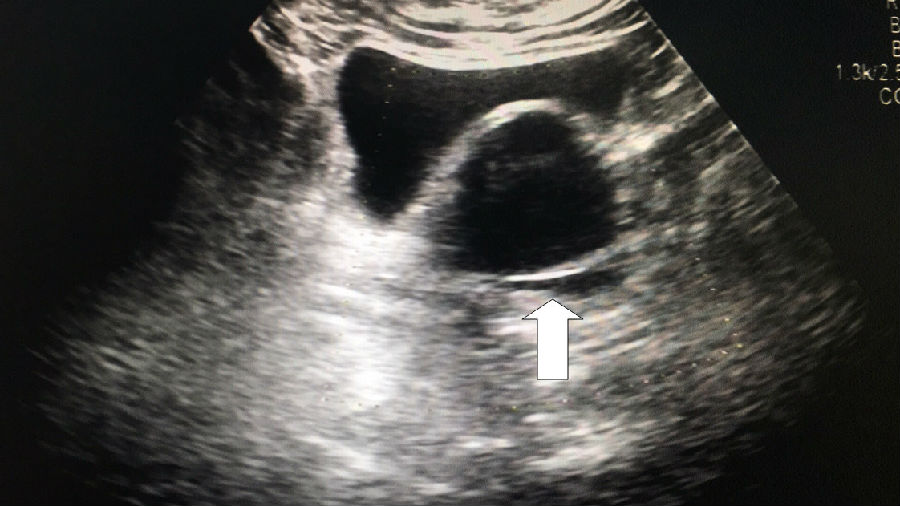

到深圳市中医院B超检查发现,右侧附件有肿瘤,而且它居然有7公分这么大

16:08手术正式开始,杜主任先用阴道拉钩打开林阿姨的阴道,暴露后穹隆,从后穹隆切开50px大的小孔,进入腹腔,置入“自制手套式”Trocar,镜下可以看见肿瘤在右侧卵巢,大小约175px×175px×150px,和周围的组织肠管、侧盆壁居然都有不同程度的粘连。